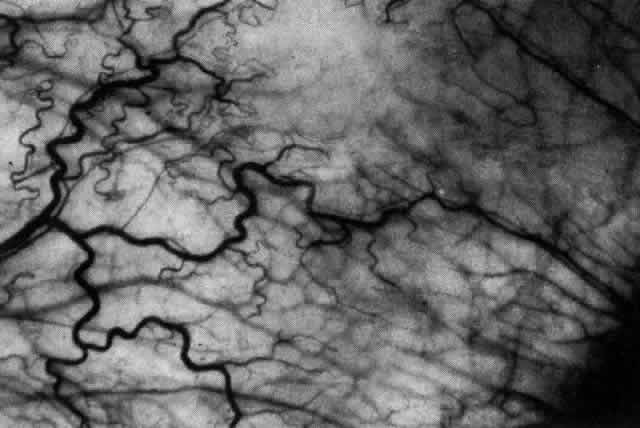

The redness of simple episcleritis may be intense, varying from a fiery-red or a brick-red discoloration to a mild red flush, but it does not have the bluish tinge that is seen in scleritis. The distribution is usually sectorial but can involve the whole anterior segment of the globe. The episcleral vessels are engorged but retain their normal radial position and architecture (Figs. 13 and 14; Color Plate 1A). In simple episcleritis, there is a diffuse edema of the episcleral tissues. These tissues are sometimes infiltrated with gray deposits that appear yellow in red-free light. Surprisingly, the eye is rarely tender to the touch.

Fig. 13. Infiltration of the episclera in which the superficial episcleral vessels show maximal congestion. Conjunctival vessels are slightly congested, as is the deep episcleral plexus, whose irregular criss-cross pattern can be seen deep to the radially arranged superficial episcleral plexus.

Fig. 14. Diffuse inflammation. Superficial vessels are maximally engorged and retain their radial pattern and architecture. (See Figures 27 and 34.) (Watson PG: Connective tissue disorders and the eye. In: Recent Advances in Ophthalmology, Vol 5, pp 214–277. London, Churchill-Livingstone, 1975)